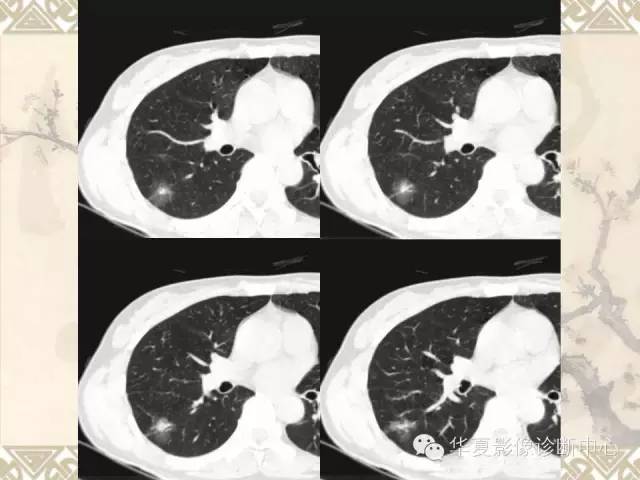

肺内磨玻璃样结节的影像诊断与处理对策